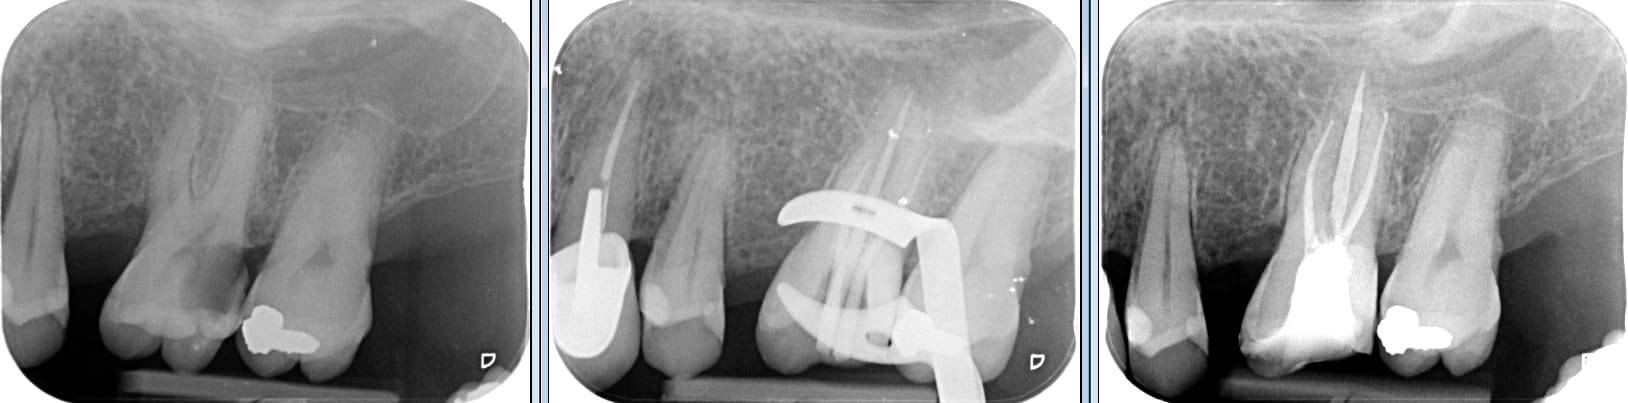

Pas du tout... Des reconstitutions pré-endo j'en fait quasiment sur chaque molaire. Ça me prend a peu près... 2min et une capsule d'equia forte a 3e. Je demande 50e d'honoraires. Ca ne vaut pas plus.

Demander 100 ou 200e, une reconstitution pré-endo, c'est s’asseoir sur le tact et mesure.

Reconstitution pre endo ilntq8 - Eugenol